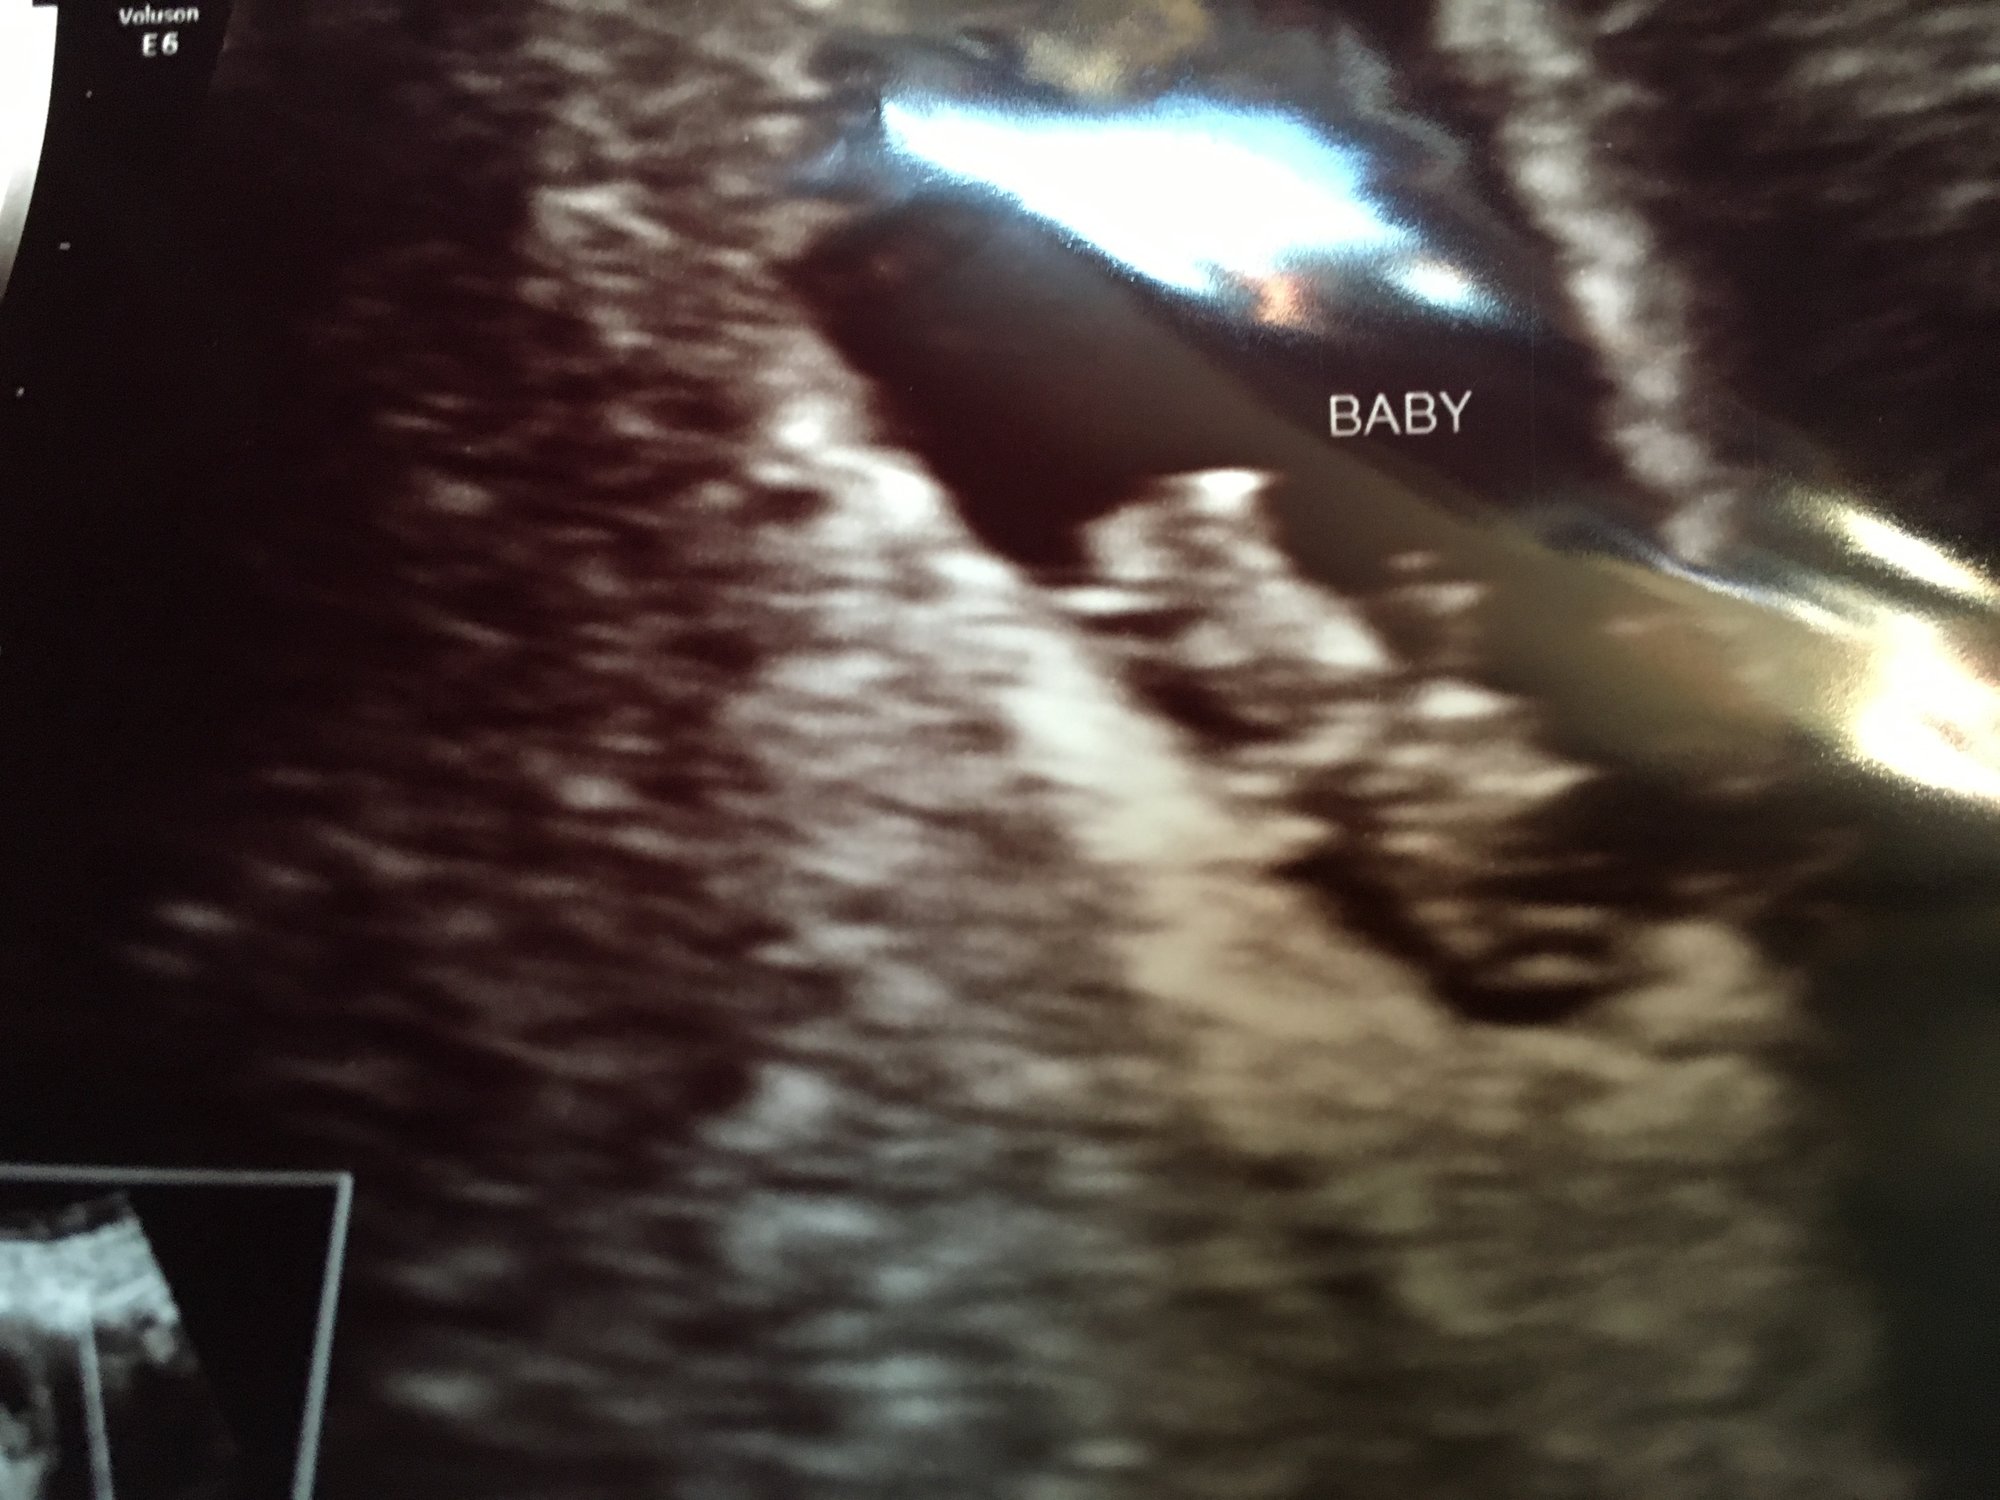

Sorry it's enormous but I suck at computers. I'm measuring exactly 8 weeks today and heart rate was 166. It was so nice to know that all the nausea and boob pain is not all in my head. There's a real person in there!